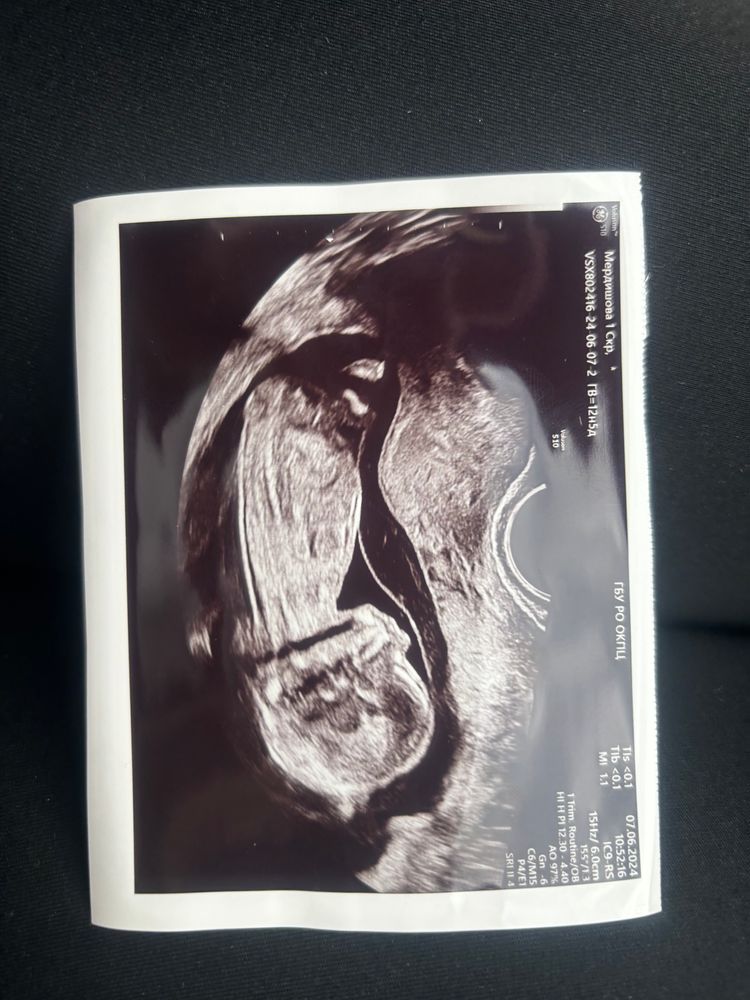

Какой пол?

Тут на фото нет бугорка))) поэтому пальцем в небо

Татьяна Мердишова, где именно? Я не вижу здесь бугорок!

Татьяна Мердишова, нашла коммент. Это и не бугорок. Он выглядит иначе.

Думаю у вас будет девочка

На девочку похожа)

Ханна, бугорок маленький вперед а не вверх торчит

Девочка

Татьяна Мердишова, вот это бугорок половой Изображение Если бы торчал кверху резко,предположили бы мальчика. А если бугорок прямо или вниз, то девочка) а далее вместо бугорка будет кофейное зёрнышко. До 16 недели ещё будет бугорок, плюс/минус неделя.